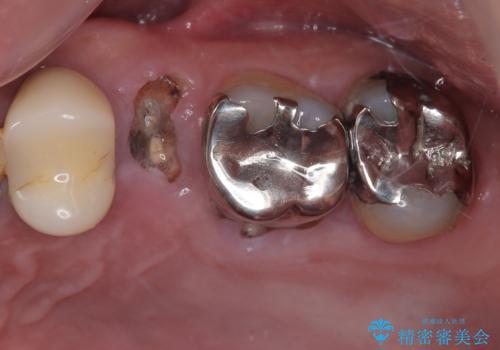

- 左上の小臼歯の被せものが外れてしまったことを主訴に来院された患者様の症例です。

診査・診断を行ったところ、

歯質の残存量(フェルール)が確保できない状態

歯根が短く、矯正治療で挺出を行っても将来的な予後が不良

と判断されました。

このようなケースでは、無理に被せ物をやり直しても再び脱離を繰り返したり、破折してしまう可能性が高く、長期的な安定は期待できません。そのため、今回は抜歯が最も妥当な治療選択と診断しました。